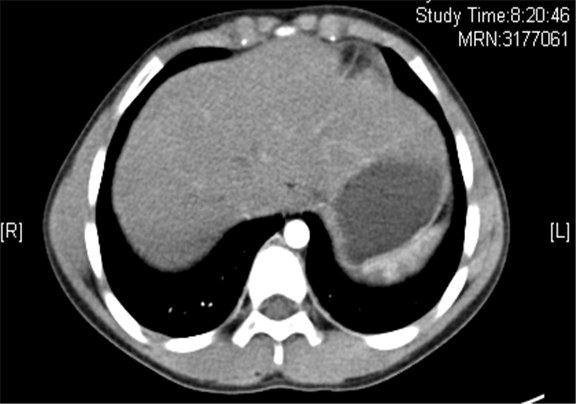

上腹部增强CT示:右侧肾上腺区占位性病变,考虑恶性肿瘤,右侧肾上腺神经母细胞瘤可能性大,请结合临床综合评价。

术前CT检查:

动脉期

静脉期

平衡期